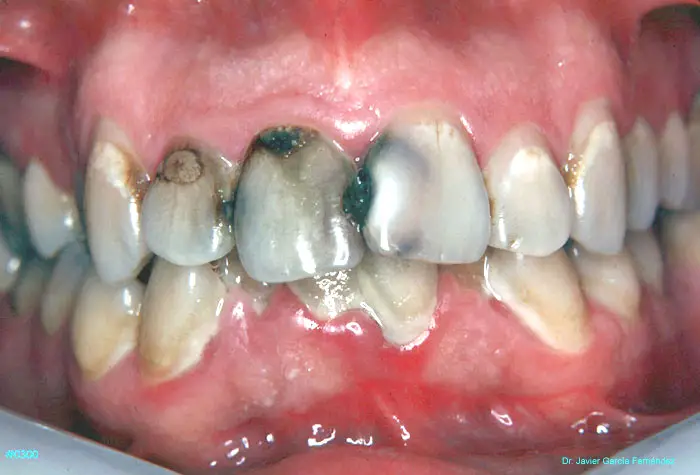

ATLAS DE CIRUGIA PERIODONTAL

image345